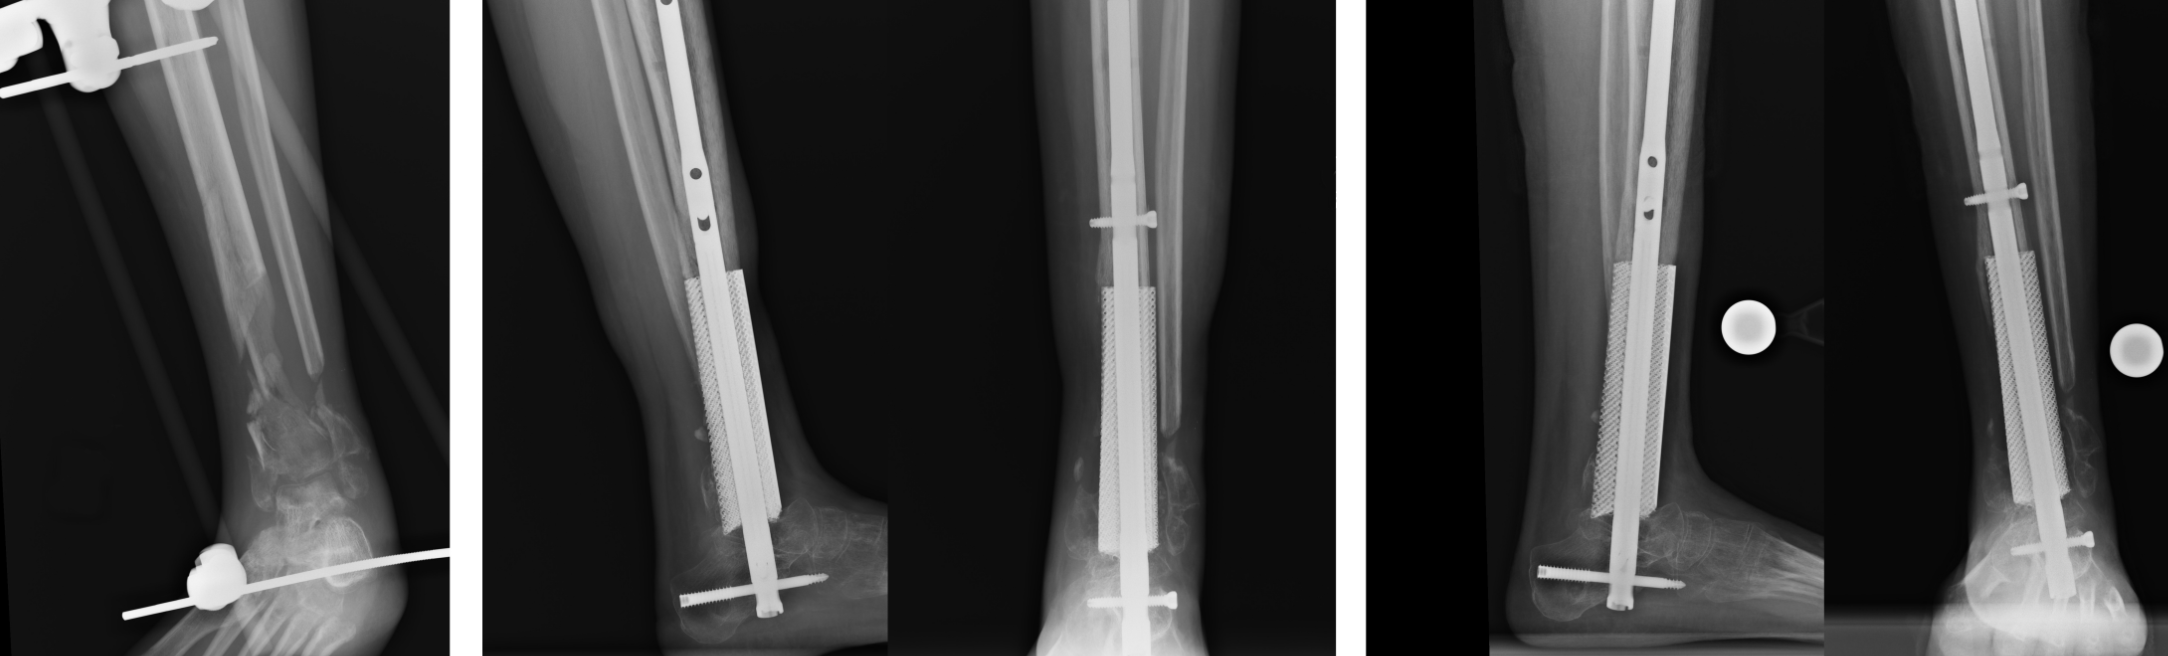

A few years ago, Gall was responsible for designing and printing custom titanium implants for a young patient who suffered severe calf bone damage in a car accident. Samuel Adams, an orthopedic surgeon at Duke University, explained: “The patient’s condition was very critical at the time. The patient had a lot of bone loss. Instead of amputating the patient like other hospitals, we implanted a 3D-printed implant in the patient’s body. The implant replaces the lost bone.” Gall worked with Adams to use the patient’s CT scan to manufacture and design the scaffold to support the patient’s weight while healing and growing new bone around the titanium structure. After analysis, they designed a 4-inch piece of porous solid titanium to replace the patient’s damaged distal tibia.

Gall points out that the challenge with leg or ankle implants is that they must support bone growth while supporting the patient’s wound healing process; other complex design factors include the external shape of the implant, the skeleton of each patient shape, and how bones grow.

△restor3d’s 3D printed implant replaces the distal tibia. Image courtesy of Duke Health.